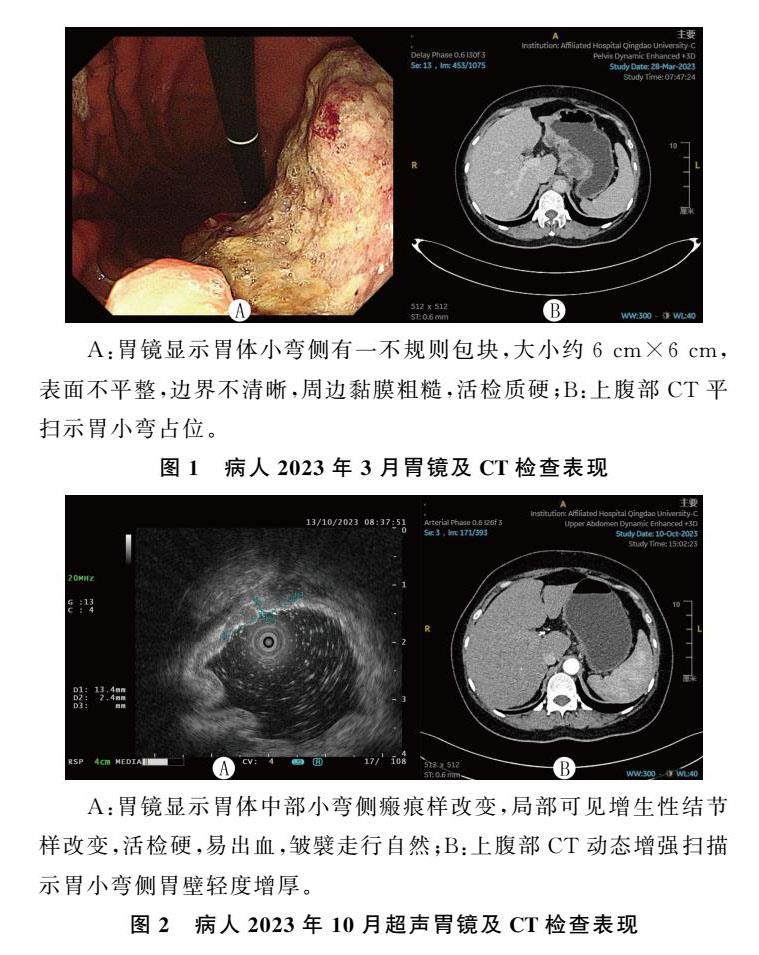

经验介绍 | 卡度尼利单抗治疗胃腺癌完全缓解1例并文献复习

经验介绍 | 卡度尼利单抗治疗胃腺癌完全缓解1例并文献复习